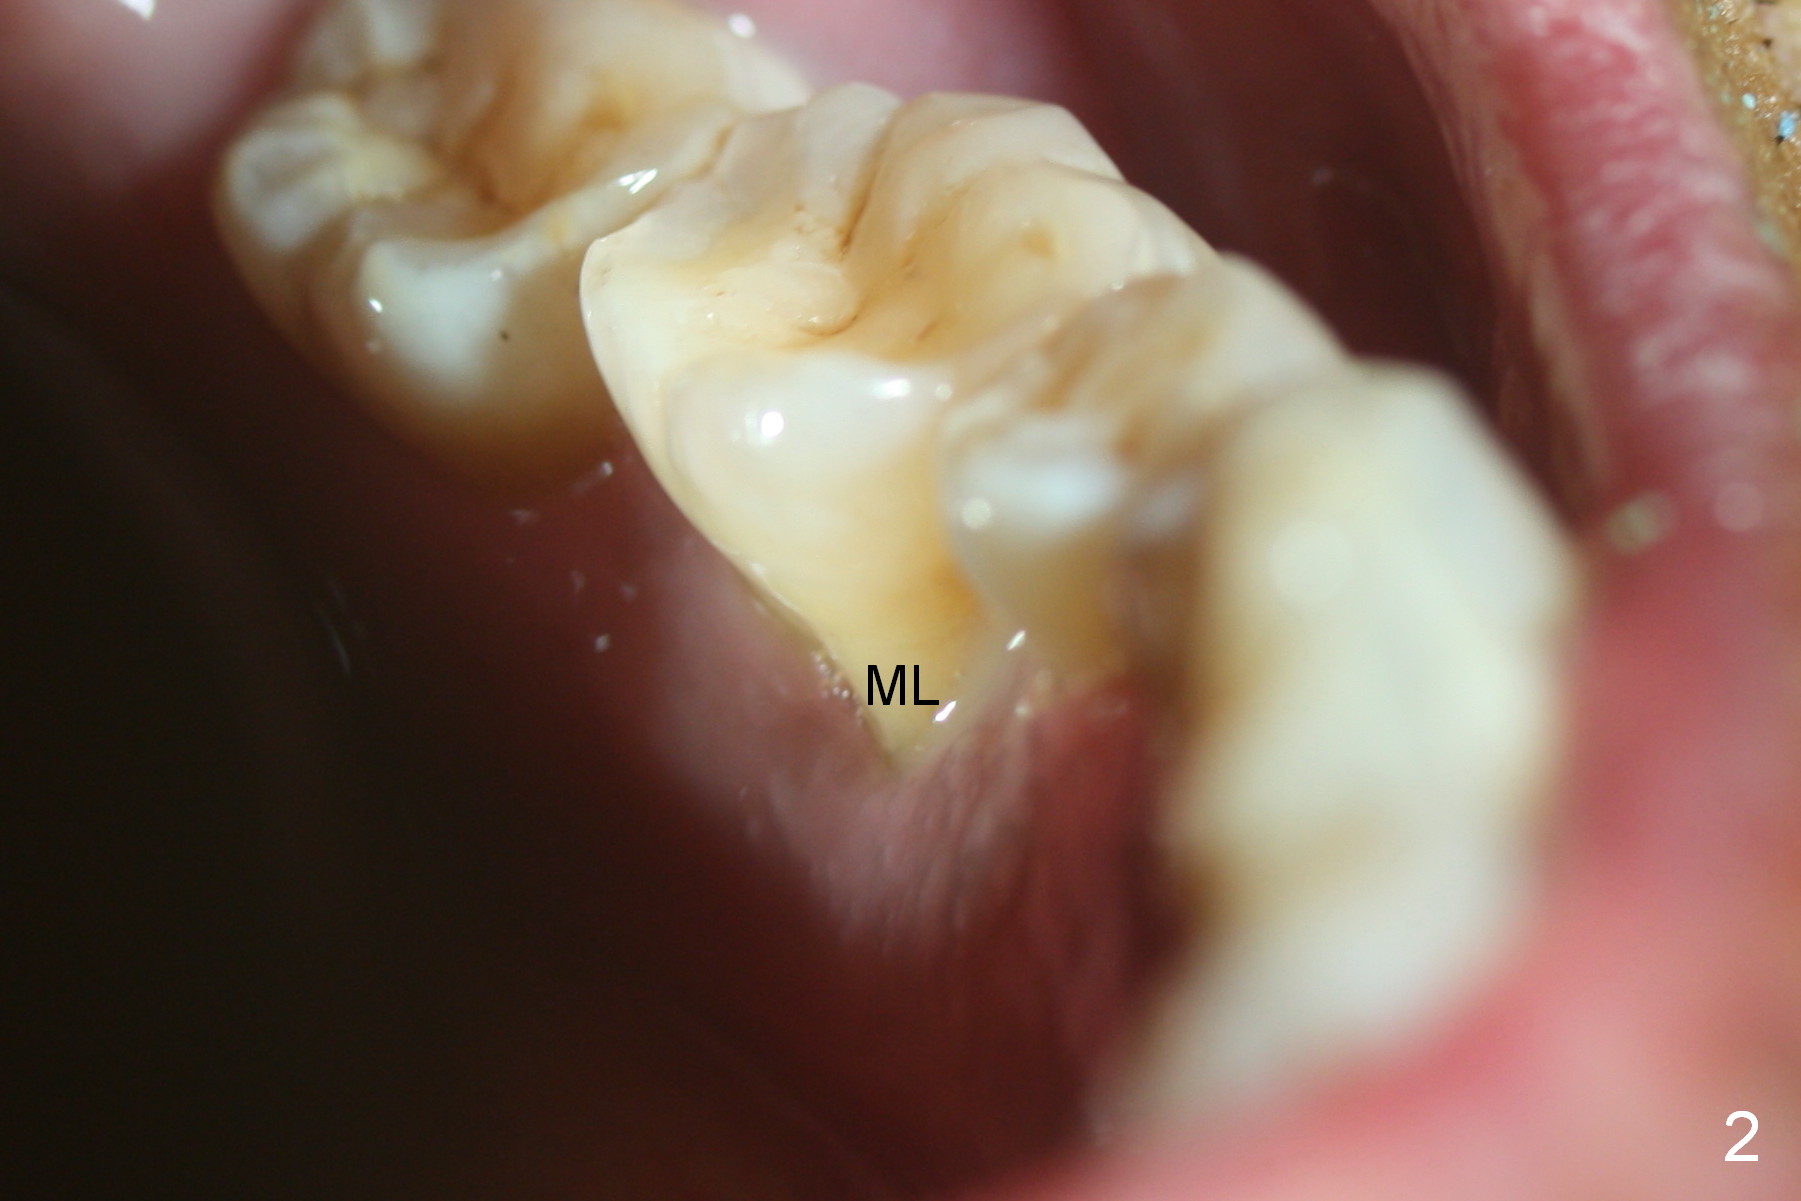

Considering the severe bone loss in the meisal socket, socket preservation is indicated if immediate implant is not feasible.  Preop exam shows that the mesiobuccal gingival recession (Fig.1 MB) is not as severe as the mesiolingual one (Fig.2 ML).  Because of oozing from the mesial socket, buccal envelop incision is made with flap raising to increase visibility.  Probably due to periodontal infection, pain control is difficult.  Osteotomy buccal to the Inferior Alveolar Canal proves to be risky.  In addition, osteotomy in the mesial socket is more difficult than the distal one (Fig.3).  Once the osteotomy depth is determined relative to the superior border of the Inferior Alveolar Canal (4 mm), the osteotomy depth increases by 2 mm.  A 5.5x10 mm implant is placed with insertion torque ~ 35 Ncm (Fig.4); a 15 ° angled abutment (5.5 mm in diameter, 4 mm in cuff) is placed mesially.  Then the abutment is turned lingually favorable for restoration (Fig.5), the remaining socket is filled with allograft/Osteogen (*) and Collagen Plug.